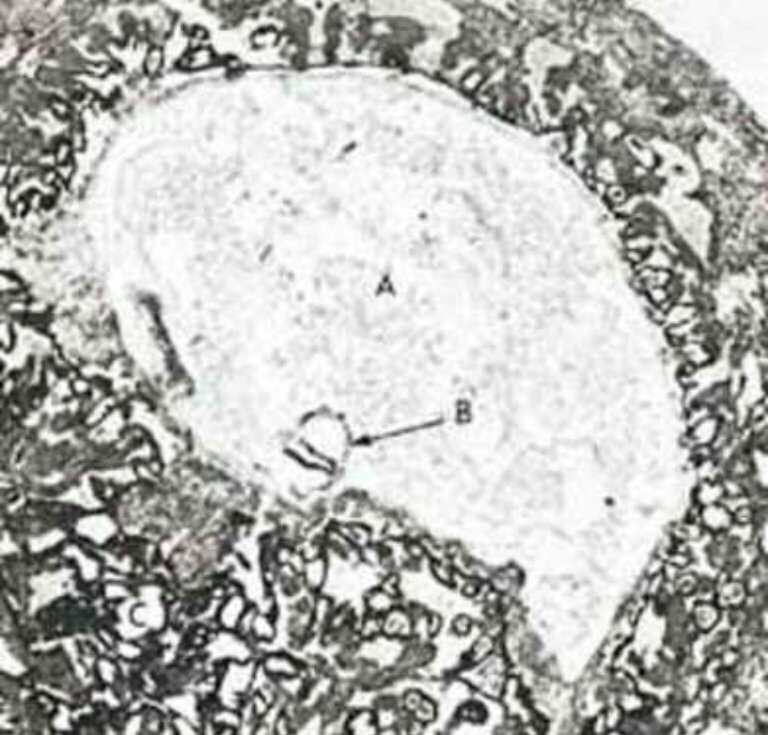

Mukjizat Alquran: Segumpal Darah yang Melekat | Republika Online

Subhanallah, Inilah Mukjizat Alquran tentang Embriologi | Republika Online

Sains Jumpa Quran: 11. PERKEMBANGAN EMBRIO MANUSIA : PERSPEKTIF SAINS & QURAN